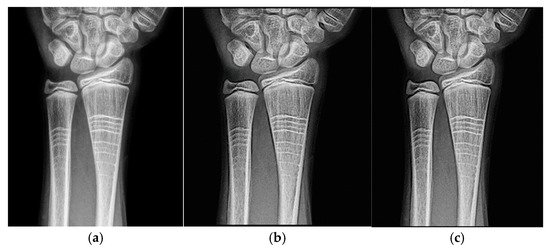

Figure 1a shows the original image of a knee radiograph, which serves as a reference for comparing the effects of the applied filters. Figure 1b shows the image processed with the Cream filter and d = 1.4, which shows improved contrast and sharpness due to reduced scattering and improved bone architecture. Figure 1c shows the image processed with the Bosso filter (d = 1.4), which smooths noise and improves edge definition, resulting in a clearer and more detailed image.

Figure 1. Knee images (a) original, (b) processed with the Cream filter, (c) processed with the Bosso filter.